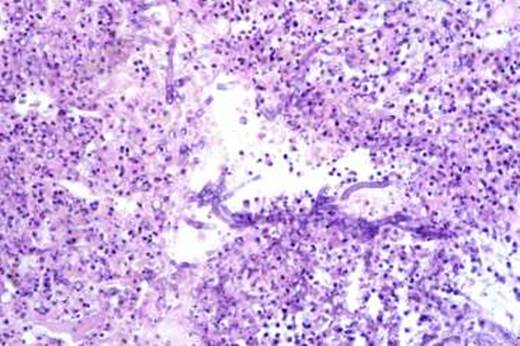

Сап — инфекционное заболевание однокопытных животных, вызывается P. mallei и характеризуется специфическим воспалением органов с образованием гранулем. Животные инфицируются возбудителем алиментарным путем, реже через конъюнктиву и слизистую оболочку носа (когда на них попадают капельки гноя, содержащие сапные микробы), и через кожу. В естественных условиях первичные поражения возникают в легких, куда сапные микробы попадают с кровью. Вокруг микробов скапливаются нейтрофильные лейкоциты, соседние альвеолы заполняются серозно-фибринозным экссудатом с лейкоцитами. Начинают размножаться мезенхимальные клетки с образованием зон эпителиоидных, лимфоидных клеток. Центральная часть очага быстро подвергается некрозу, ядра лейкоцитов распадаются на глыбки (кариорексис). В дальнейшем, некротический центр расширяется за счет распада прилегающих эпителиоидных клеток и тканей органа. Макроскопически сформировавшийся сапный узелок округлой формы, плотной консистенции. В легких сапные поражения могут быть в виде милиарных, крупноочаговых узелков и в виде сапной бронхопневмонии. Эти формы поражения сходны с туберкулезными поражениями.